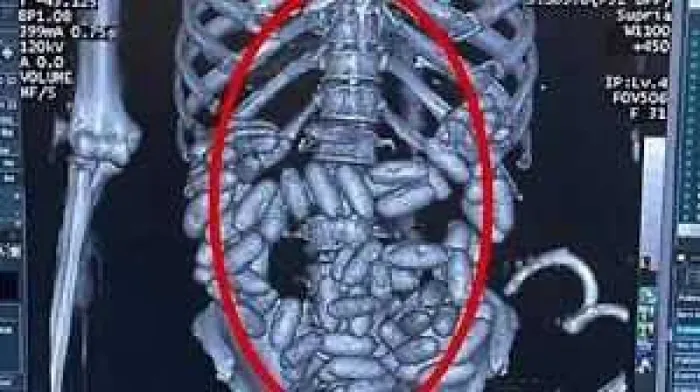

Kolombiya'da uyuşturucu ticaretine devam eden ve kısa sürede Güney Amerika'dan Avrupa'ya kokain ticareti yapan uluslararası bir suç örgütünün lideri durumuna gelen Müldür, uyuşturucuyu Brezilya'dan "yutucu kurye" yöntemiyle kuryelerin midelerinde dünyanın birçok ülkesine göndermeye başladı.

Müldür'ün kuryelerinden Nijerya asıllı R.E. (22) de 4 Mart 2019'da Sao Paulo'dan havayolu ile İstanbul'a gelmesinin ardından, midesinde tespit edilen 1 kilogram ağırlığındaki 82 kapsülle yakalandı.